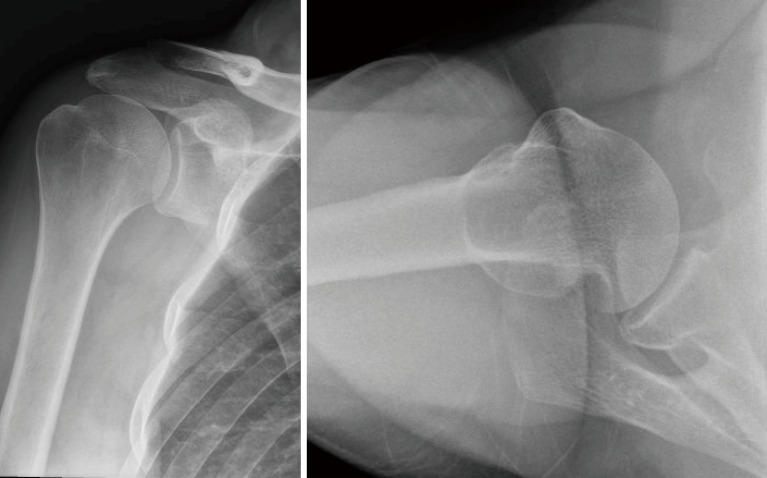

Key content and findings: ASI typically occurs from abduction and external rotation forces. Diagnosis relies on clinical assessment and imaging (magnetic resonance imaging or computed tomography), to evaluate soft tissue and bony injuries. Non-operative management is associated with high recurrence rates in contact athletes. Surgical options include arthroscopic Bankart repair (ABR) with or without remplissage, open Bankart repair (OBR), or bone block procedure such as Latarjet procedure or distal tibia allograft. All of which have been shown to decrease risk of recurrence and have a high rate of return to sport. The choice of procedure depends on the extent of soft tissue and bony involvement and the athlete's individual demands. ABR with glenoid bone loss >13.5% have high recurrence rates, therefore, additional procedures such as remplissage or bone block procedures should be considered.

Conclusions: ASI in the contact athlete is a common and challenging injury to manage. Surgical intervention provides superior outcomes in terms of stability and recurrence prevention compared to non-operative management of ASI in the contact athlete. Patient-specific considerations including level of sport, patient goals, and timing of season are considerations for treatment. Labral injury with <13.5% of glenoid bone loss and on-track Hill-Sachs lesion ABR is recommended, labral injury with 13.5-20% of glenoid bone loss with off-track Hill-Sachs lesion ABR with remplissage or OBR with capsule shift is recommended, and if >20% then bone block procedure is recommended.